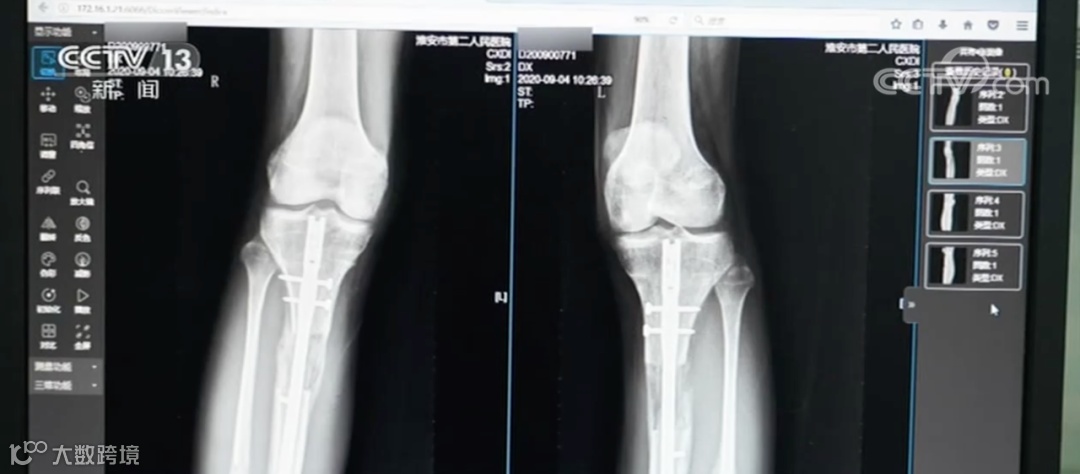

近日,江苏省淮安市第二人民医院接诊了一名特殊患者。这名患者因为对自己的身高不满,在国外做了“断骨增高手术”,结果导致双腿严重感染无法行走,甚至面临终身残疾。

此外,“断骨增高手术”还具有多方面的危害。王磊表示,在实施断骨增高手术时,外固定“增高器”的钢针要穿透患者的双腿,可能损伤腿部的血管、神经组织,造成感染,甚至引发骨髓炎,造成残疾。同时,断骨增高手术会造成血管损伤,严重的腿部血液供应障碍可能造成下肢组织坏死。